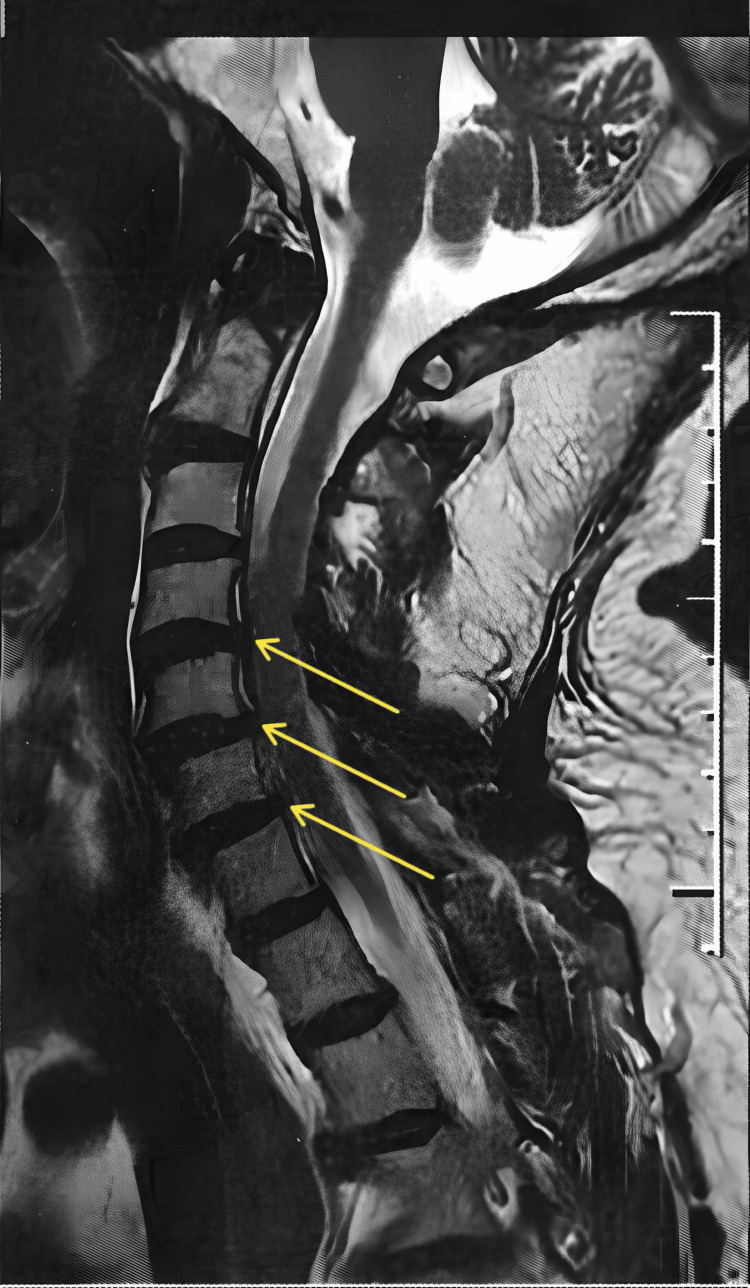

Spondyloarthritis (SA) is a chronic inflammatory disease that predominantly affects the spinal column. SA-related pain can be intense, persistent, and disabling. Studies with cannabis have been conducted involving patients with refractory epilepsy, multiple sclerosis, Parkinson’s disease, sleep disorders, and chronic pain. Cannabidiol is the major non-psychotropic component of cannabis, has anti-inflammatory and analgesic properties, and exerts anxiolytic and mood-stabilizing effects. This paper reports a case of a 72-year-old male with SA, with mild stenoses of the spinal canal at C4-C5 and C5-C6 and stenoses of the left neural foramina at C3-C4, C4-C5, C5-C6, and C6-C7. The use of cannabidiol in our patient achieved satisfactory results in the control of pain related to cervical spondyloarthritis.

A 72-year-old, white, male, diabetic, hypertensive, and retired physician with spondyloarthritis and mild stenoses of the spinal canal at C4-C5 and C5-C6 and stenoses of the left neural foramina at C3-C4, C4-C5, C5-C6, and C6-C7 (Figure 1) presented with constant neuropathic pain in the cervical spine and left shoulder and arm for more than one year, numbness on the left side of the face, diminished muscle strength, and pain intensity of 8 on the visual analog scale (VAS) of 1 to 10.